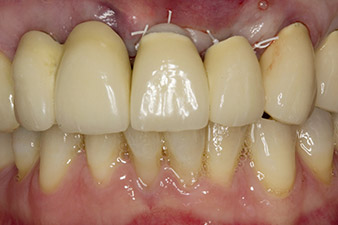

Following primary healing, the soft tissues were shaped using the basally lined bridge. Two months later the site was exposed by a slightly palatal alveolar ridge incision (Fig 2). The dimensions of the alveolar bone proved to be sufficient at position 22. Figures 2 and 4 show the preparation of the implant bed, the tapping and the implantation using Implantmed.

In order to compensate for the periodontal bone loss and achieve an aesthetically pleasing result, the implantation was combined with guided bone regeneration (GBR) with xenogenic replacement material and a collagen membrane

(Fig. 5 and 6).